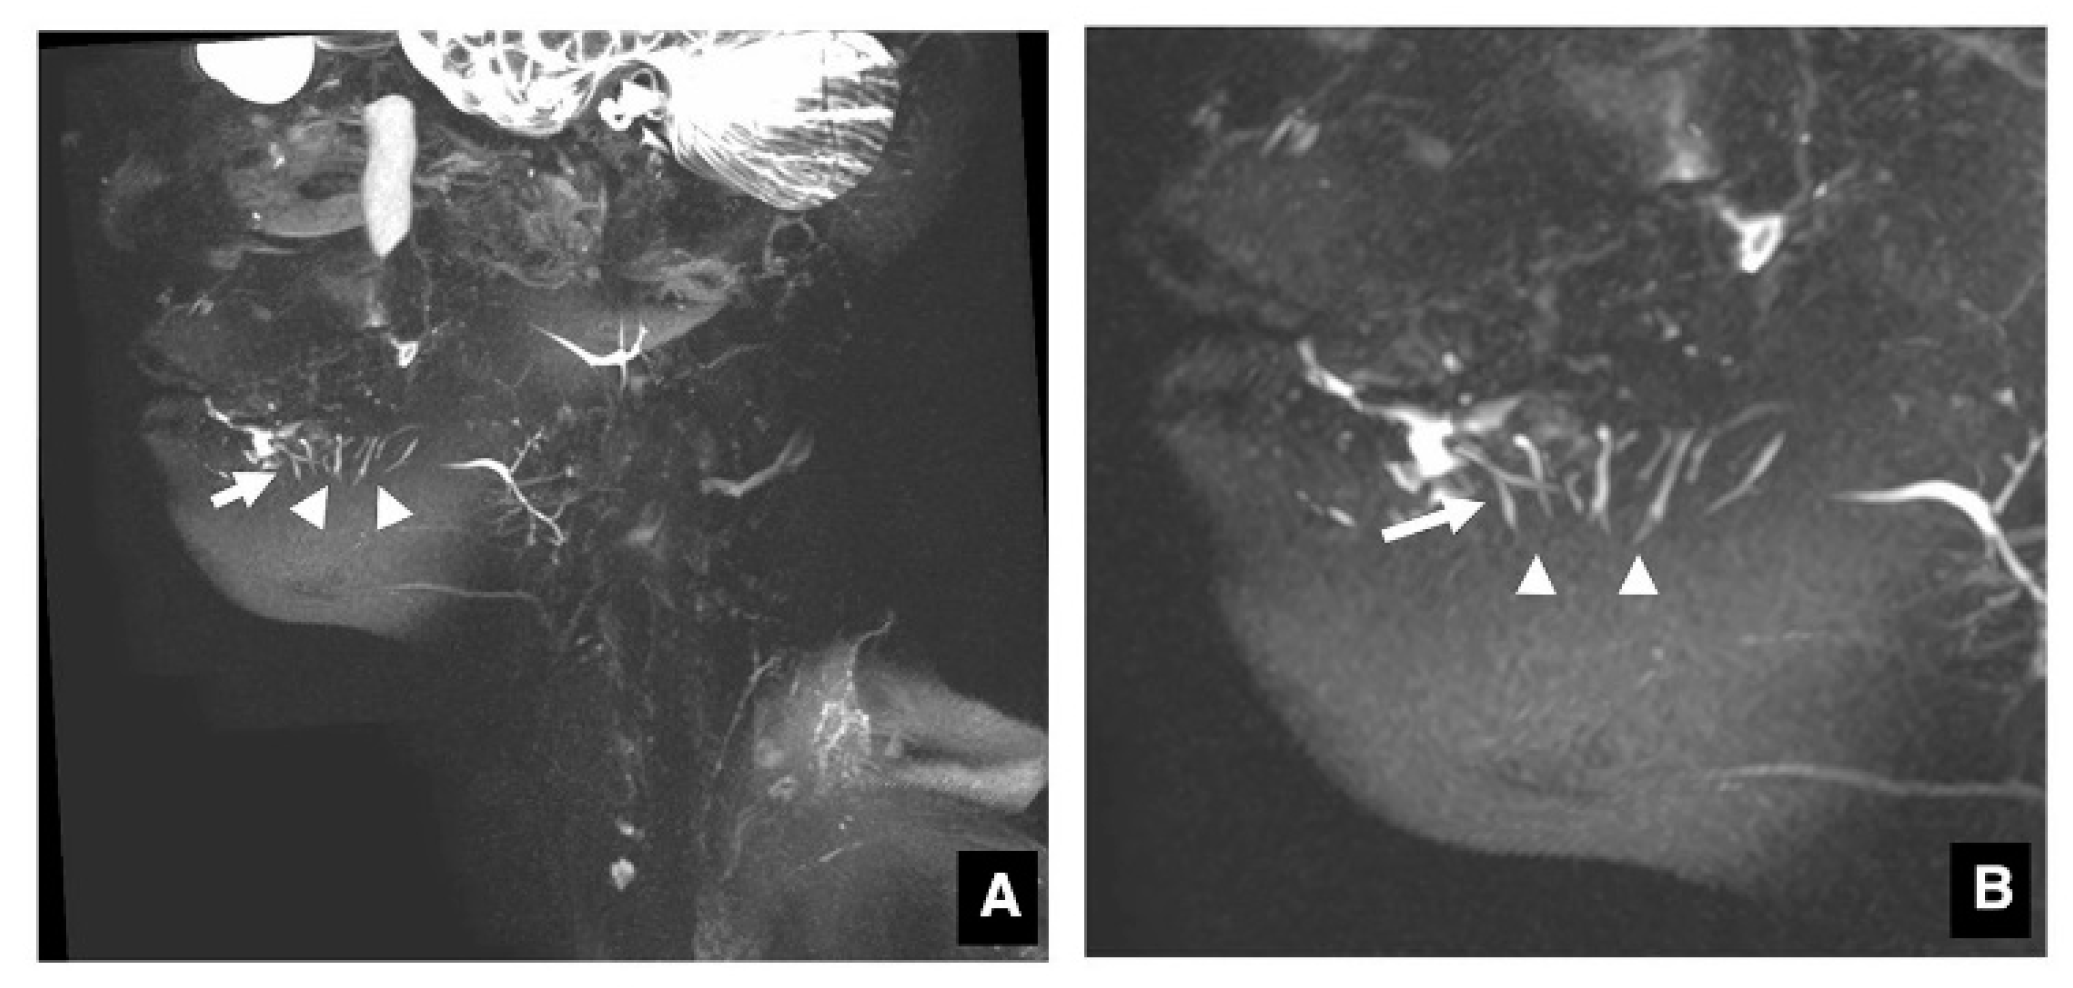

3.1. Visualization of Sublingual Gland Ducts by MR Sialography

3.2. Function of Sublingual Gland Ducts Evaluated by Dynamic MR Sialography

3.3. Clinical Application of MR Sialography for Patients with Sublingual Gland Diseases